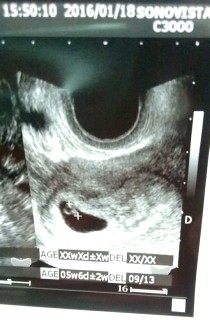

生理周期で計算すると8w4dだけど、大きさで考えると6w位だと言われました(*^_^*)マイペースに育ってくれれば嬉しいです(*^O^*)大きさは7ー8mmでした(*^_^*)心拍も確認できて、そのまま母子手帳もらって来ました♪